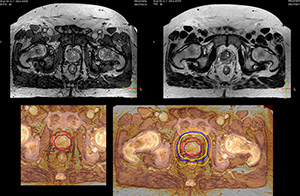

“When a patient registers, first CT simulation and MR simulation are done, followed by CT-MR registration on Pinnacle3. Then the target and normal organ delineation is performed on MR images. Meanwhile we create a reference CT image for online treatment and localization correction. During the treatment phase we can perform additional MRI scans to visualize the anatomy changes and create an adaptive plan. This plan basically adapts the treatment plan to the changes.” “Along with its great benefits, MR has introduced some new challenges,” Dr. Stevens says. “Radiation therapy teams generally have no experience with MR. The Philips training helped us to implement fully the things we can do with the Ingenia MR-RT system. So the training, as well as having a good MR physicist, is critical.”

“The biggest problem for CT-based planning, especially in prostate, is you can’t see the cancer very well,” says Dr. Stevens. “On CT it can be quite challenging to see the edge of the prostate especially at the apex. When the edge of the prostate can’t be delineated well on CT, radiation oncologists will increase their margins a little bit so they don’t miss it, but that can also increase toxicity.” “Using MR, the prostate is well delineated. We quickly see the edges of cancerous tumors like in prostate cancer, and as normal structures can be defined, we can optimize the treatment plan to protect these organs and their normal function. This can potentially improve the outcome. And it improves workflow as well. We can contour more quickly, confident that the tumor is going to be in the field.” “The Ingenia 3.0T MR scanner provides high resolution allowing us to make scans fast for the patients. It also gives the potential to include methods like MR spectroscopy and diffusion weighted Imaging, which we’re in the process of doing right now,” Dr. Stevens adds.